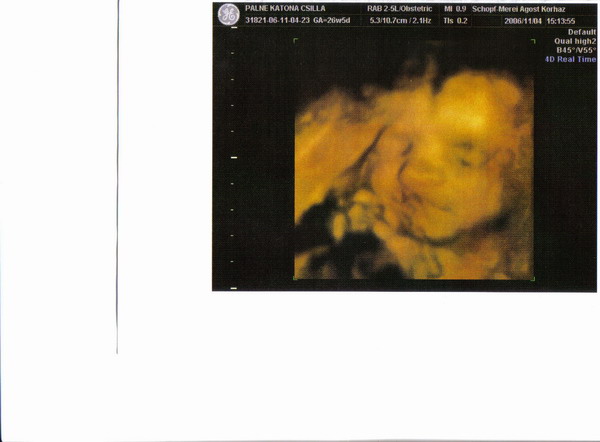

Holnap megyünk 4d-re, remélem jól sikerül és tudok majd képet feltenni a kis huligánról!